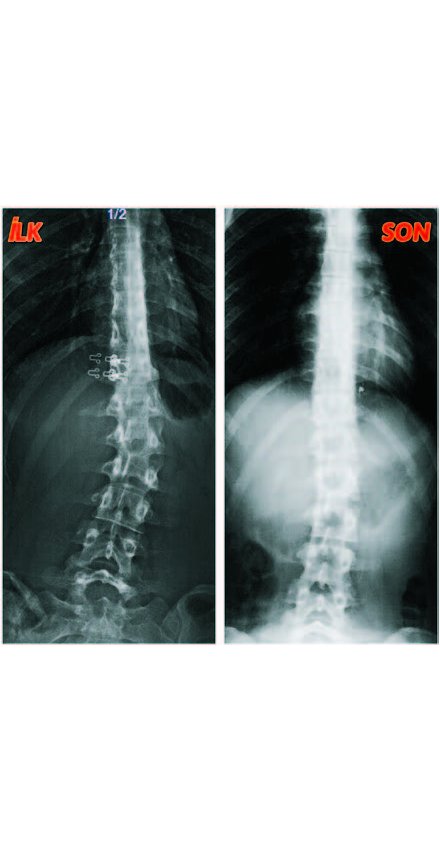

Merkezde Elif Hanım ile tanıştım. Hikayemi dinledi ve yaptığı incelemeler sonucunda omurgamın tamamen düzelebileceğini söyledi. Ardından da benim için özel bir egzersiz programı hazırladı. Yaklaşık 2 aydır, haftanın 3 günü Elif Akıncı Pozitif Yaşam Merkezi’ne devam ediyorum. Haftalık programımda egzersiz olarak 3 schrot ve 2 rubatonik pilates uygulaması yapıyoruz. Bu egzersizlerle 2 ay gibi kısa bir sürede 23 derece ile başladığım skolyozum 10 derece geriledi. Elif Hanım, egzersizlere düzenli devam ettiğim taktirde omurgamdaki eğriliğin 0 dereceye kadar düzelebileceğini söyledi. Elif Akıncı Pozitif Yaşam Merkezi, alanında uzman güler yüzlü bir ekiple danışanlarına hizmet veriyor. Buradaki egzersizler kişilere detaylı şekilde anlatılıyor. Randevularıma geleceğim günleri iple çekiyorum. Zorlu egzersizlere rağmen buraya gelmek benim için çok eğlenceli. Pandemi sürecinde girdiğimiz zorunlu kısıtlamaların yanı sıra egzersizlerin benim için aktiviteye dönüşmesi beni daha da motive etti. Yaşadığım şikayetlerin benzerlerini bana aktaran okul arkadaşlarımın hepsine Elif Akıncı Pozitif Yaşam Merkezi’ni önerdim. Sosyal medyada görüp merkeze gelmekte tereddüt edenlere önerim, omurgayla ilgili bir sorun yaşıyorlarsa gönül rahatlığıyla Elif Hanım’a danışabilirler. Memnun kalacaklarına eminim. Kendisine çok teşekkür ediyorum.”